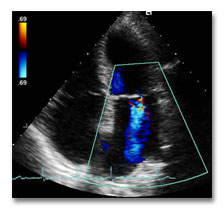

Die Echokardiographie ist eine Ultraschalluntersuchung vom Herzen.

Hierzu werden von einem sog. „Schallkopf“ Ultraschallwellen ausgesandt, vom Körper reflektiert und dann vom Schallkopf wieder empfangen. Hierdurch kann man die Organe bildlich darstellen und Bewegungen aufzeichnen.

Der zusätzliche Einsatz eines Farbdopplers macht die Richtung und Geschwindigkeit des Blutstroms sichtbar. Hierfür ist keine Vorbereitung notwendig, der Patient muss lediglich auf der linken Seite liegen. Die Untersuchung ist absolut schmerzlos.